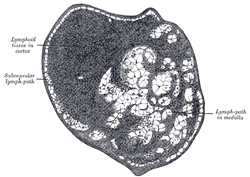

| The prostate has a rich lymphatic plexus surrounding the gland and a wide-meshed subcapsular plexus. | 24 |

| FIG. 597 Section of small lymph gland of rabbit. X 100. (See enlarged image) | | |

| The uterus is provided with a subserous plexus, the deeper lymphatics are uncertain. Subepithelial plexuses are found in the vagina. | 26 |

| The ovary has a rich superficial plexus and a deep interstitial plexus. | 27 |